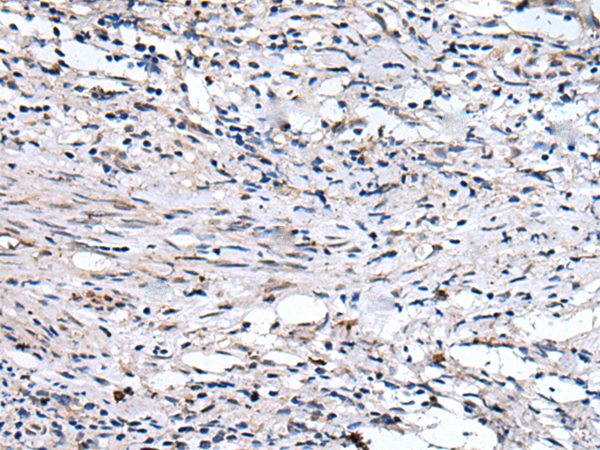

IHC positive control:

Human breast cancer

IHC Recommend dilution:

25-100